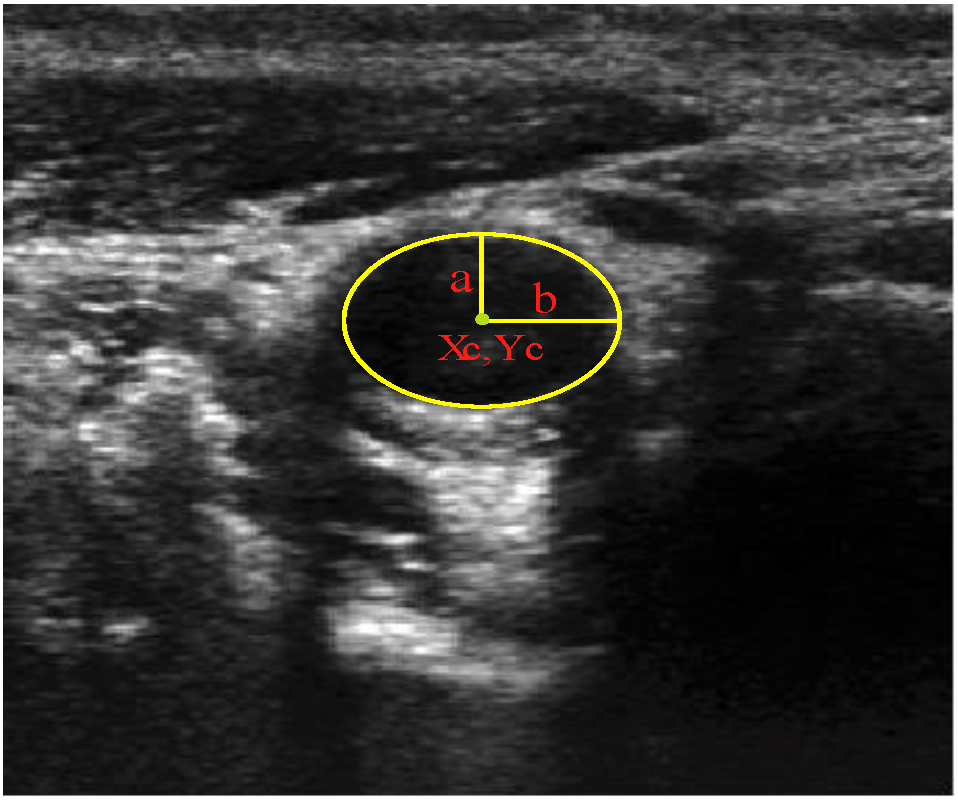

2.2.1. Feature Extraction

, and the magnitude projection image,

, and the magnitude projection image,  .

.

determinates the level of speckle noise, and therefore, it allows the control of the diffusion over time in Image (I).

determinates the level of speckle noise, and therefore, it allows the control of the diffusion over time in Image (I).

), and the pixel orientation, (

), and the pixel orientation, (  ), vector by means of function Av, which defines the angle between both vectors. The second objective function, f𝑔, Equation (22), aims to find shapes with a higher echogenicity given by the LIP-Sobel gra2-dient, Gv. To avoid the gradient generated by small variations in the intensity of the image, a threshold scheme is utilized. The function is set to the gradient if the threshold is higher than a defined value; otherwise, a penalization is applied to avoid the discontinuity in the shape of the ellipse and the gradient map. The third objective function, fb, Equation (23), acts in a similar way as the previous one, but in this case, a binary map, Bv, is used. Finally, the fourth objective function, fFRS, Equation (24), will guide the ellipse into the center of the artery using the FRS map. Once all the objective functions have been defined, the fitness function can be expressed as shown in Equation (25), where the weights, α1,α2,α3,α4, are incorporated for each respective objective function. After empirical tests, it was found that those values fixed to α1 = 100, α2 = 2, α3 = 100, α4 = 30 of the proposed method achieve satisfactory results.

), vector by means of function Av, which defines the angle between both vectors. The second objective function, f𝑔, Equation (22), aims to find shapes with a higher echogenicity given by the LIP-Sobel gra2-dient, Gv. To avoid the gradient generated by small variations in the intensity of the image, a threshold scheme is utilized. The function is set to the gradient if the threshold is higher than a defined value; otherwise, a penalization is applied to avoid the discontinuity in the shape of the ellipse and the gradient map. The third objective function, fb, Equation (23), acts in a similar way as the previous one, but in this case, a binary map, Bv, is used. Finally, the fourth objective function, fFRS, Equation (24), will guide the ellipse into the center of the artery using the FRS map. Once all the objective functions have been defined, the fitness function can be expressed as shown in Equation (25), where the weights, α1,α2,α3,α4, are incorporated for each respective objective function. After empirical tests, it was found that those values fixed to α1 = 100, α2 = 2, α3 = 100, α4 = 30 of the proposed method achieve satisfactory results.